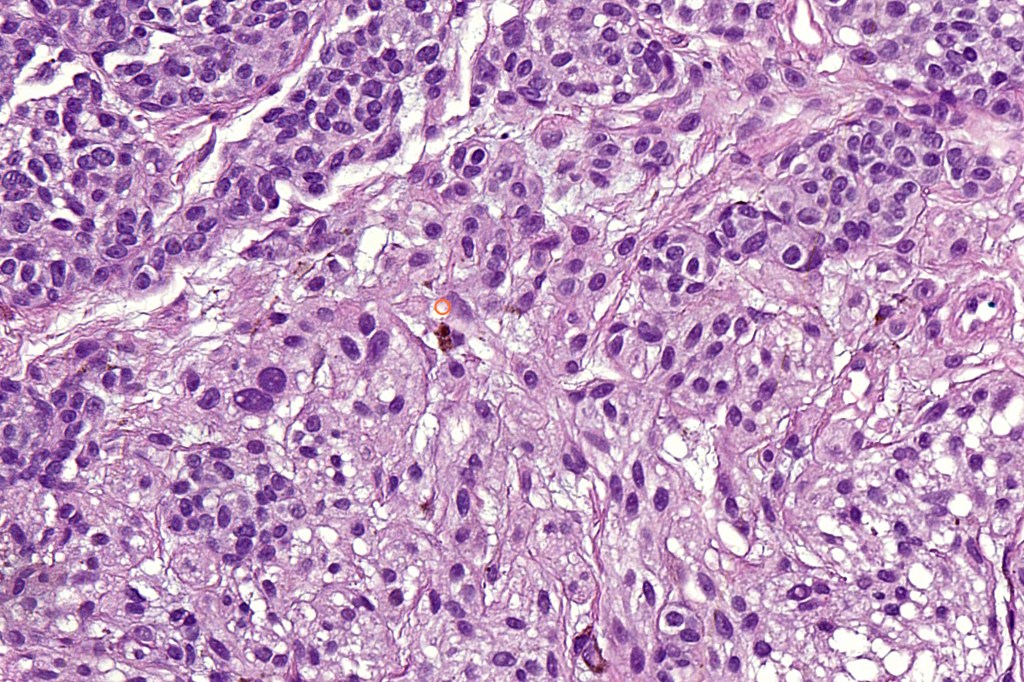

•May affect the tumor in part or whole

•Enlarged cells with copious eosinophilic, foamy or clear cytoplasm (some authors include melanoma with clear cell change in the same category)

•Variable pigmentation

•Nuclei vesicular or hyperchromatic

•Pleomorphism is not generally marked and indeed can be very subtle

•Variable mitotic activity

•DPAS granules

•Thought to be a result of abnormal or degenerative melanosome change